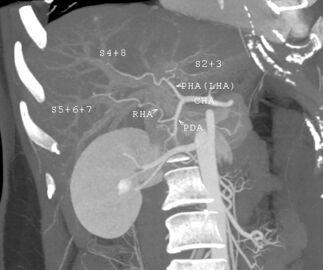

-

فحص بالتصوير المقطعي المحوسب يظهر فيه الكبد والوريد البابي.